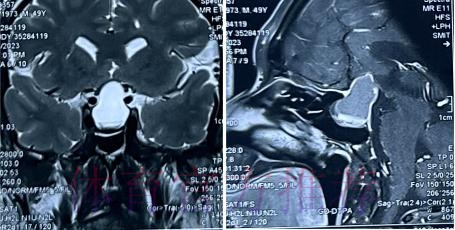

在高速对抗的现代足球里 现场肉眼和赛后情绪往往会放大对伤情的判断 一名球员倒地呻吟或无法坚持比赛 很容易被解读为韧带断裂 或肌肉严重撕裂 但真正决定恢复周期的关键因素 通常要到核磁共振检查之后才会明朗 因为核磁能在较早阶段清晰显示软组织 肌肉 韧带以及骨结构的微小损伤情况 对伤情做出更接近真相的分级判断 塞巴略斯此次就是典型案例 初步观感可能让人联想到更严重的伤病 但核磁提示伤情相对可控 没有出现完全断裂或大面积撕裂 也就意味着他不需要漫长的康复旅程 只要遵循医学建议 科学负荷管理 就有机会用较短的时间重新回到训练场和比赛中

塞巴略斯这一类型的技术中场 通常触球频繁 变向急促 需要大范围穿插跑动 在这种比赛习惯下 肌肉和韧带承受的累积负荷极高 尤其在密集赛程和高压对抗中 任何一次小小的失衡或强硬对抗 都可能放大为潜在伤病 因此外界对他伤情格外敏感 并非夸张反应 而是基于过往大量案例得出的经验判断 从厄德高 德布劳内 再到其他同类型中场 很多球员都在职业生涯某个阶段与伤病长期共存 一旦错过最佳治疗和恢复窗口 轻伤有可能拖成旧患 进而影响球员的爆发力 节奏控制能力乃至职业寿命 在这一背景下 经核磁共振检查确认 塞巴略斯伤情没有预期严重 其实反映的是球队在医疗体系 与负荷管理上的相对成熟 至少在第一时间 做到了科学评估 而不是情绪化处理